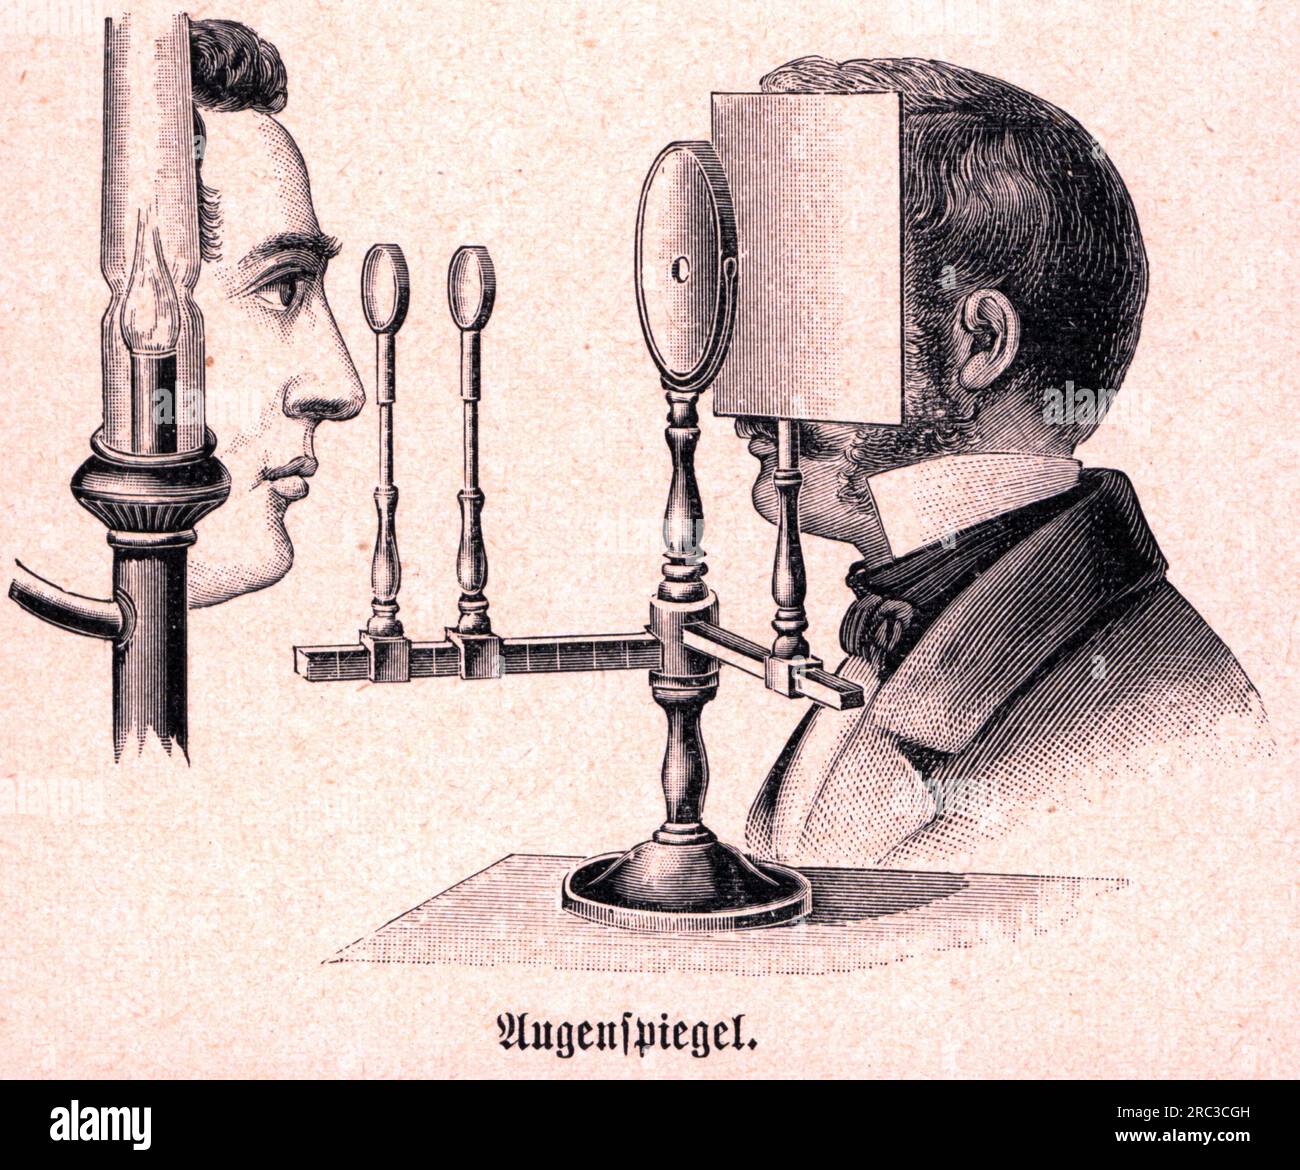

medicine, ophthalmology, ophthalmoscope, after Hermann von Helmholtz, 1850 / 1851, wood engraving, ARTIST'S COPYRIGHT HAS NOT TO BE CLEARED Stock Photohttps://www.alamy.com/image-license-details/?v=1https://www.alamy.com/medicine-ophthalmology-ophthalmoscope-after-hermann-von-helmholtz-1850-1851-wood-engraving-artists-copyright-has-not-to-be-cleared-image558183377.html

medicine, ophthalmology, ophthalmoscope, after Hermann von Helmholtz, 1850 / 1851, wood engraving, ARTIST'S COPYRIGHT HAS NOT TO BE CLEARED Stock Photohttps://www.alamy.com/image-license-details/?v=1https://www.alamy.com/medicine-ophthalmology-ophthalmoscope-after-hermann-von-helmholtz-1850-1851-wood-engraving-artists-copyright-has-not-to-be-cleared-image558183377.htmlRM2RC3CGH–medicine, ophthalmology, ophthalmoscope, after Hermann von Helmholtz, 1850 / 1851, wood engraving, ARTIST'S COPYRIGHT HAS NOT TO BE CLEARED